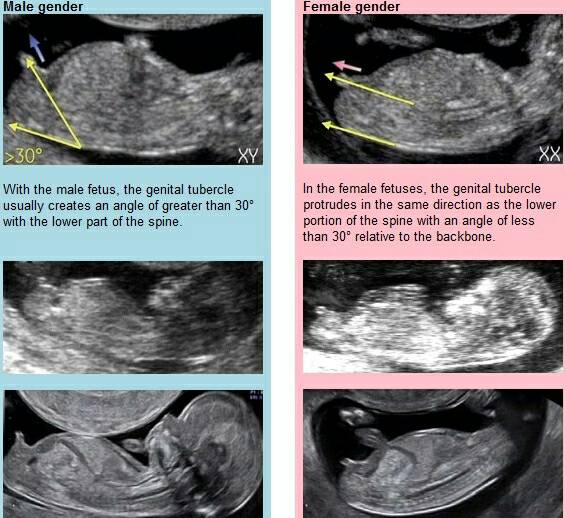

U mnie to jest bez różnicy co będzie byle było zdrowe maleństwoTaka jest różnica między chłopcem i dziewczynką. Życzę powodzenia lekarzowi. [emoji23]Zobacz załącznik 767687